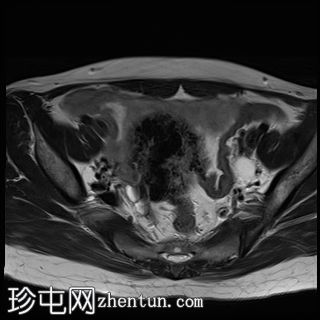

MRI

矢状位

T2加权像

子宫增大且体积较大。扩张的血管主要位于子宫后壁(符合子宫动静脉畸形)。

子宫内膜肌层交界处也存在异常。

子宫内膜腔显影清晰,外观正常。